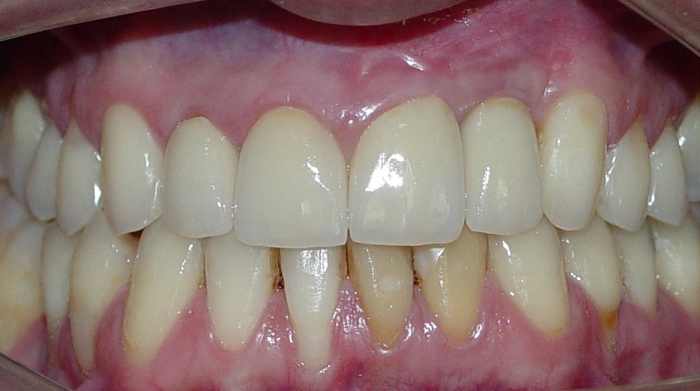

Sorriso final

Imagem final após enxerto de gengiva, troca da prótese fixa sobre o implante e tratamento reabilitador